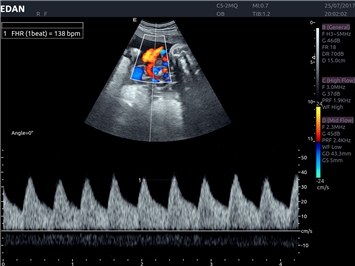

EDAN Acclarix LX4 представляет собой инновационную ультразвуковую систему, построенную на усовершенствованной платформе Acclarix. Сочетание высокого качества визуализации с интеллектуальным рабочим процессом делает эту систему оптимальным выбором для клиник, ценящих эффективность и экономичность.

• Акушерства и гинекологии

• Автоматизированные измерения в акушерстве